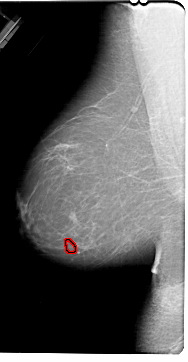

FILE: A_1830_1.LEFT_CC.OVERLAY

TOTAL_ABNORMALITIES 1

ABNORMALITY 1

LESION_TYPE MASS SHAPE OVAL MARGINS ILL_DEFINED

ASSESSMENT 4

SUBTLETY 2

PATHOLOGY BENIGN

TOTAL_OUTLINES 1

BOUNDARY